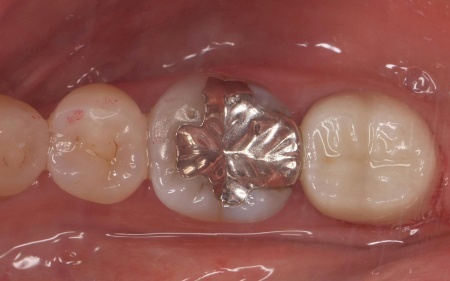

まずは歯に残っているプラスチックの詰め物を綺麗に取り除き、歯の形を整えてから型を取りました。

治療部位を長くお使いいただくためには、詰め物の噛み合わせをしっかりと確認する必要があります。完成したジルコニアの詰め物を実際に装着し、バランス良く噛めるように噛み合わせを調整して治療を終了しました。

歯の形も綺麗に回復しています。